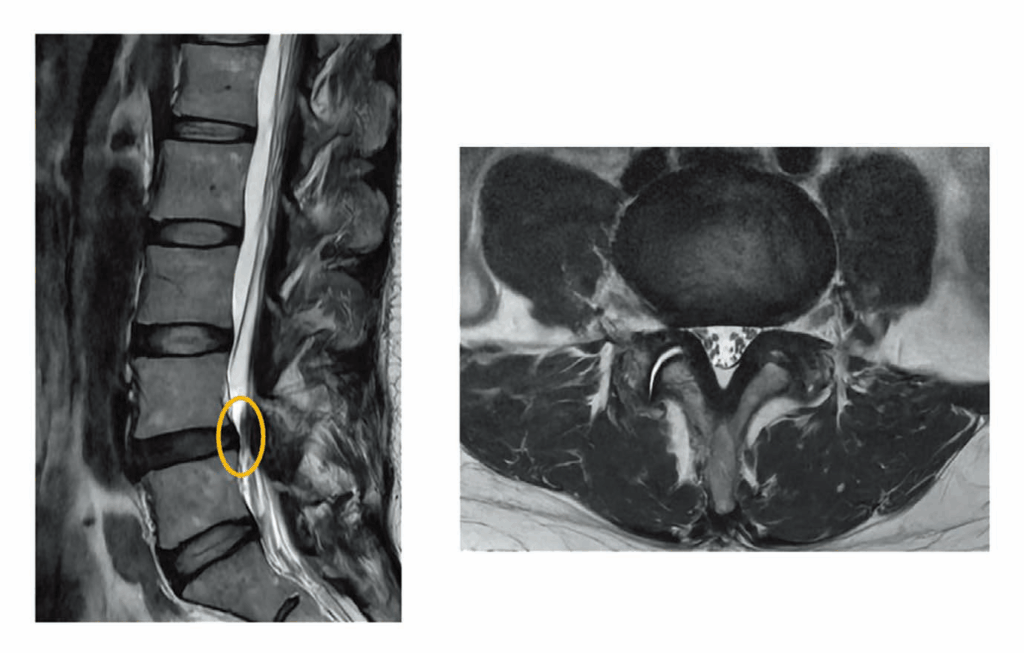

その③ 脊髄・末梢神経疾患と、今後の展望( 低侵襲手術への挑戦)

手足のしびれや痛みは、脳の異常よりも首や腰(脊椎)あるいは手足の神経の通り道が狭くなることで生じる場合が少なくありません。私は脊椎脊髄外科専門医としての視点を活かし、手根管症候群や足根管症候群、頚椎症、腰部脊柱管狭窄症などの診断と治療にも力を入れています。

現在は、正確な診断に基づく保存療法および末梢神経剥離術を中心に治療を行っていますが、将来的には、筋肉や骨、神経への負担をできる限り抑えたより低侵襲な脊椎脊髄手術(顕微鏡手術)の提供も視野に入れ、診療の質の向上に継続して取り組んでいます。

腰部脊柱管狭窄症(外側型・椎間孔狭窄)